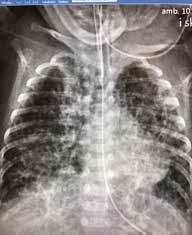

Fysiologi og hemodynamikk I de første minuttene etter fødselen skjer det store fysiologiske endringer i barnets respirasjon og sirkulasjon. Lungene tar over som gassutvekslingsorgan, og den vaskulære mostanden i lungearteriene synker som følge av økt oksygenkonsentrasjon. Når lungekarmotstanden faller, fylles lungene med blod som deretter strømmer via lungevenene tilbake til venstre hjerte halvdel (Fig.1). Dette sikrer god fylning (preload) til venstre ventrikkel som kan opprettholde et tilstrekkelig slagvolum. Slik unngår barnet store blodtrykksendringer (1, 2)

Dersom barnets lunger ikke fylles med luft, forblir lungekar motstanden høy, og det går lite blod til lungene. Avklemming av navlesnoren i denne situasjonen vil kutte blodforsyningen til barnet via navlevenen, og venstre ventrikkel får redusert fylning (preload), fordi manglende venøs retur fra placenta ikke kompenseres av økt venøs retur fra lungevenene. I tillegg øker motstanden i systemkretsløpet (afterload) på grunn av at navlearteriene er avklemt. Dette kan føre til kardiovaskulær instabilitet i de første, viktige minuttene av barnets liv og forstyrre transisjonsprosessen.

Intakt navlesnor inntil barnet har etablert pulmonal gassutveksling, gir mer stabil hemodynamikk med potensielt store gevinster, blant annet redusert risiko for hjerneblødning. Så lenge navlesnoren er intakt, kan noe gassutveksling fortsatt foregå gjennom placenta og beskytte mot asfyksi, selv om barnet er utenfor uterus.

Figuren viser mekanismer for ustabil hemodynamikk ved tidlig avnavling. Modifisert fra referanse 2, Uwins et al, med tillatelse.